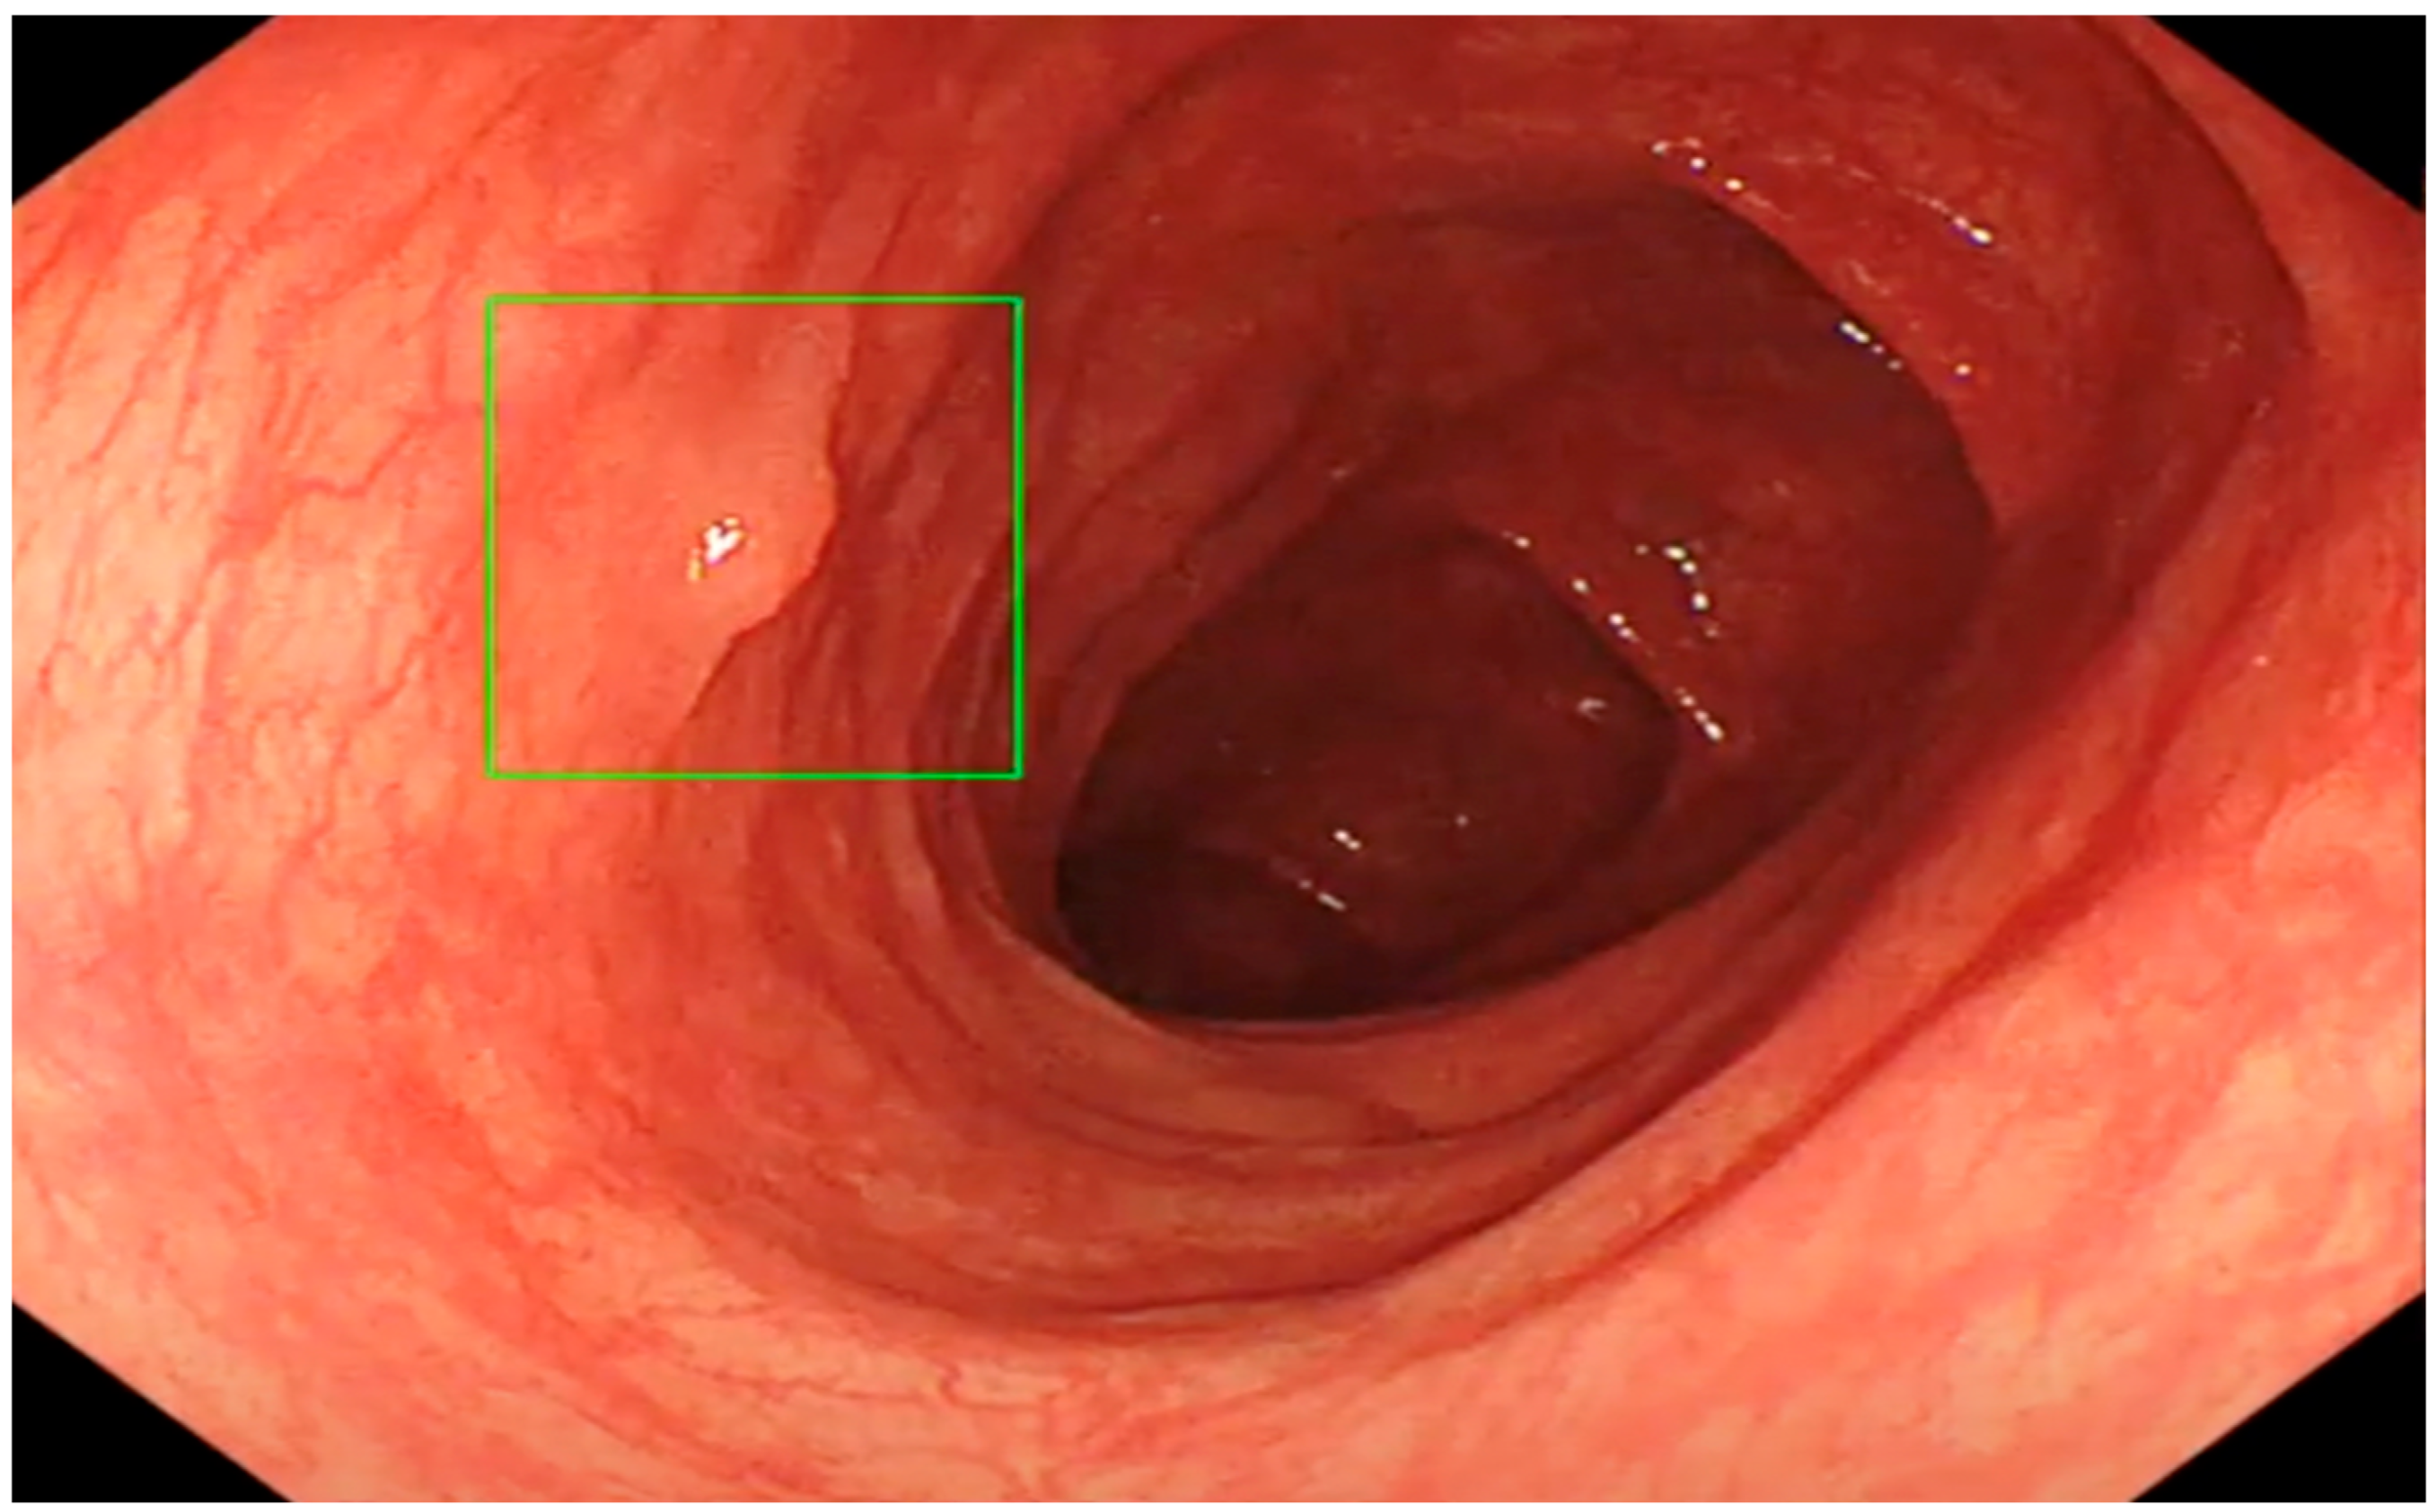

The Role of an Artificial Intelligence Method of Improving the Diagnosis of Neoplasms by Colonoscopy

The Role of Artificial Intelligence in Colonoscopy Examinations